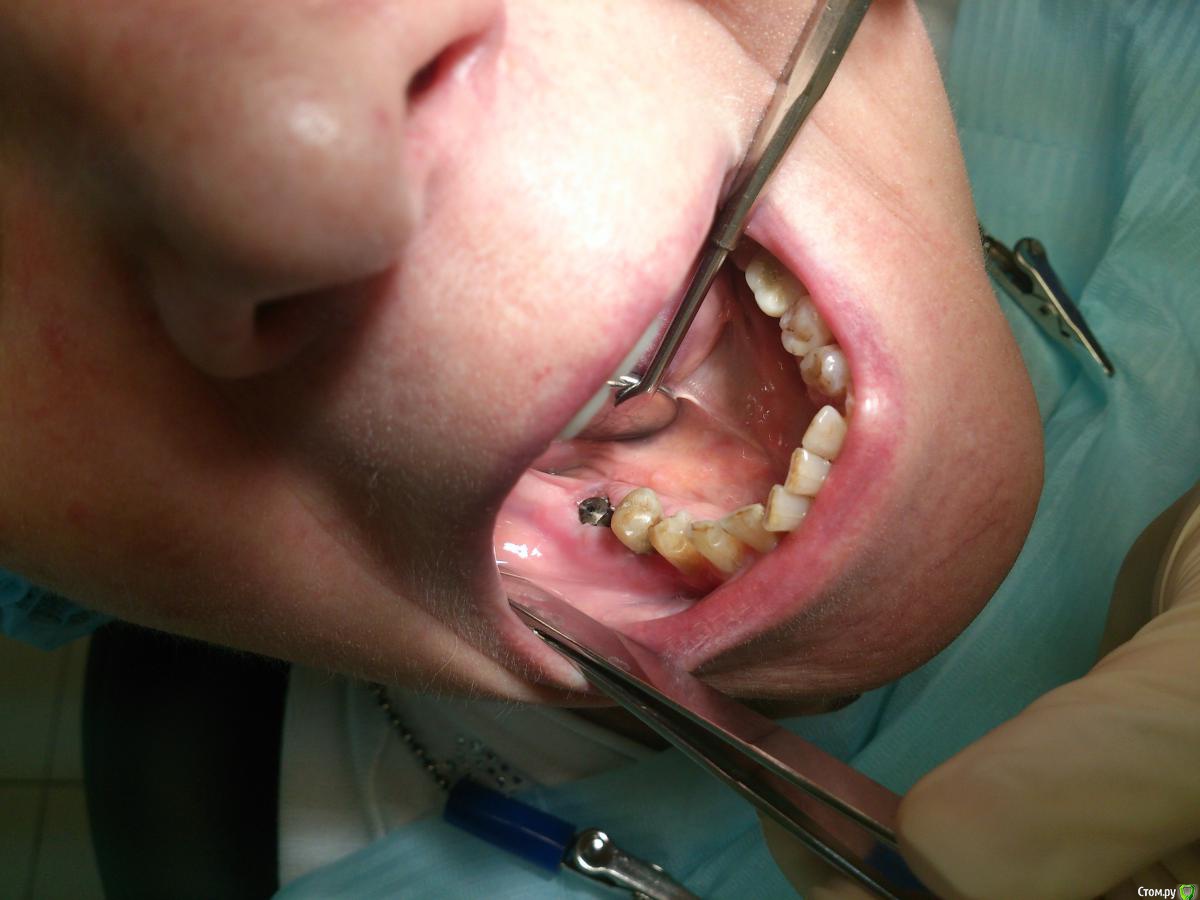

andrey_1965 Опубликовано 21 декабря, 2015 Поделиться Опубликовано 21 декабря, 2015 Ну как результат ?1.-диэпителизация подворот лоскута очень удобно,но опасно для резбы через неделю.язычно-механическая травма через 10 дней через 3недели. На временных доформирую рельеф.2. вроде ничего нештатного через 2недели A-PRF через 5недель убрал все,закрыл мембраной A-PRF две поперек,одна в доль через неделю через 13дней через 21день. Следующий осмотр будет на сроке 5 недель(думаю все сравняется) 3. через неделю 2недели 3недели,на дистальных отмываю помойку4 недели Ссылка на комментарий